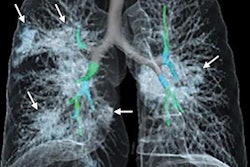

Chest radiographs were also acquired, indicating an infiltrate in the upper lobe of the left lung. The man received supplemental oxygen because of increasing dyspnea with hypoxemia, and a progressive infiltrate and consolidation were observed on the chest x-rays.